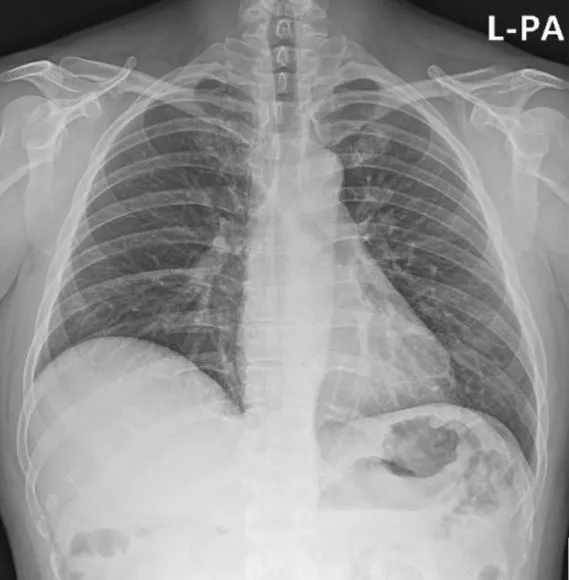

엑스레이_1.JPG

위의 사진이 제 흉부 X-ray 사진입니다. 세상에! X-ray가 투과를 했는데도 비대한 몸통은 감출 수가 없군요!